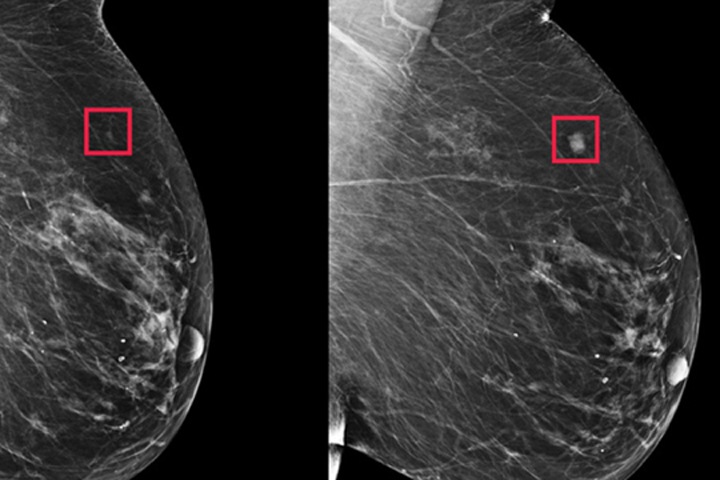

Раковая опухоль может долго не давать о себе знать и развиваться бессимптомно, поэтому очень часто ее выявляют поздно. К сожалению, всем известные онкомаркеры не могут использоваться для скрининга рака, а скорее используются онкологами для контроля противоопухолевой терапии и контроля за метастазированием. Определение уровня циркулирующих половых гормонов в крови не всегда позволяет получить полную картину, достаточную для всесторонней оценки состояния гормонального статуса женщины.